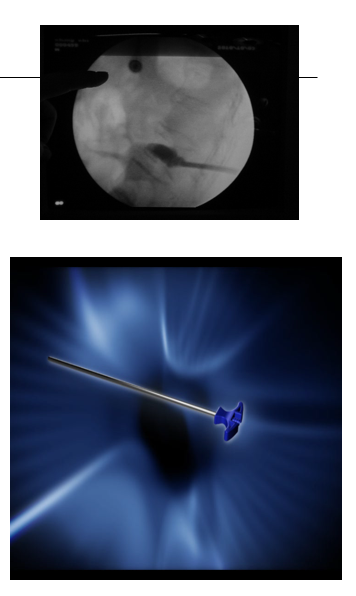

放入可扩张球囊,确保球囊位于椎体内(扩张前透视)扩张球囊:先加入2ml左右造影剂,同时时观察压力表,后每次增加造影剂0.5ml,透视至椎体扩张到满意程度,球囊系统压力控制在15个大气压左右。

注意:扩张球囊时对侧骨钻要抽出

球囊停止加压:A.终板抬高,达到治疗时B.球囊靠近骨皮质或终板时C.对比剂已注入4MLD.扩张压力已达到15个大气压左右